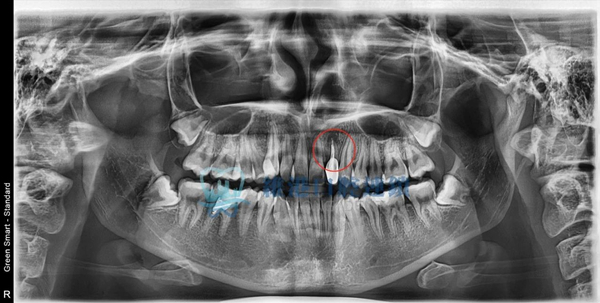

根尖囊腫案例展示

嚴重案例